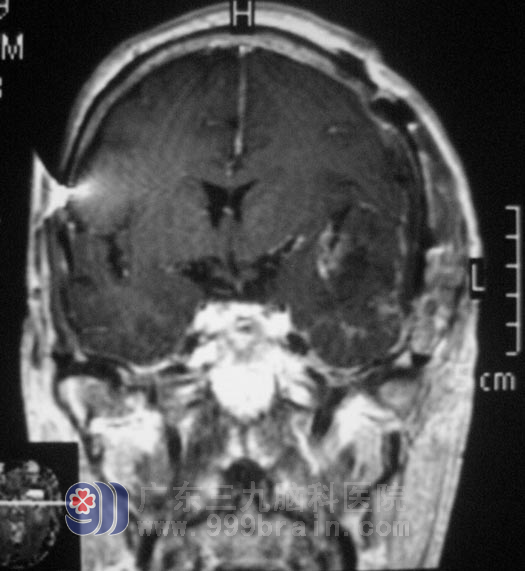

经普通脑电图检查提示轻中度异常脑电图,左侧脑区慢波稍有明显,左额区稍著,头颅MR检查提示:左侧蝶骨嵴占位性病变,左侧大脑镰旁占位性病变,考虑脑膜瘤可能。

完善相关检查后,鲁明主任主刀,行左侧翼点入路蝶骨嵴脑膜瘤切除术+颅内压监护探头置入术,术中可见颞叶处肿瘤血供丰富,肿瘤主要位于硬膜下及颞窝内,包膜完整,基底部位于蝶骨嵴处,大小约4.0cm×4.7cm×5.9cm左右,在显微镜下将肿瘤全切,手术非常顺利。术后老张恢复良好,没有出现异常不适。病理证实为:(蝶骨嵴)纤维型脑膜瘤,WHO I 级。住院九天即满意出院。